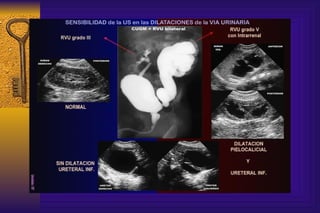

Como detectamos anormalidades de los riñones o de las vías urinarias La ecografia renal permite identificar la morfología renal  y es útil para establecer calidad de las vías urinarias. Permite observar cálices y la pelvis pudiendo medir los diámetros anteroposteriores y espesor del parénquima

En las siguientes  imágenes podemos  evidenciar como se manifiestan los diversos   grados de reflujos según estudio CUMGS.

Como detectamos anormalidadesde los riñones o de las vías urinarias La ecografia renal permite identificar la morfología renal y es útil para establecer calidad de las vías urinarias. Permite observar cálices y la pelvis pudiendo medir los diámetros anteroposteriores y espesor del parénquima

Enlas siguientes imágenes podemos evidenciar como se manifiestan los diversos grados de reflujos según estudio CUMGS.